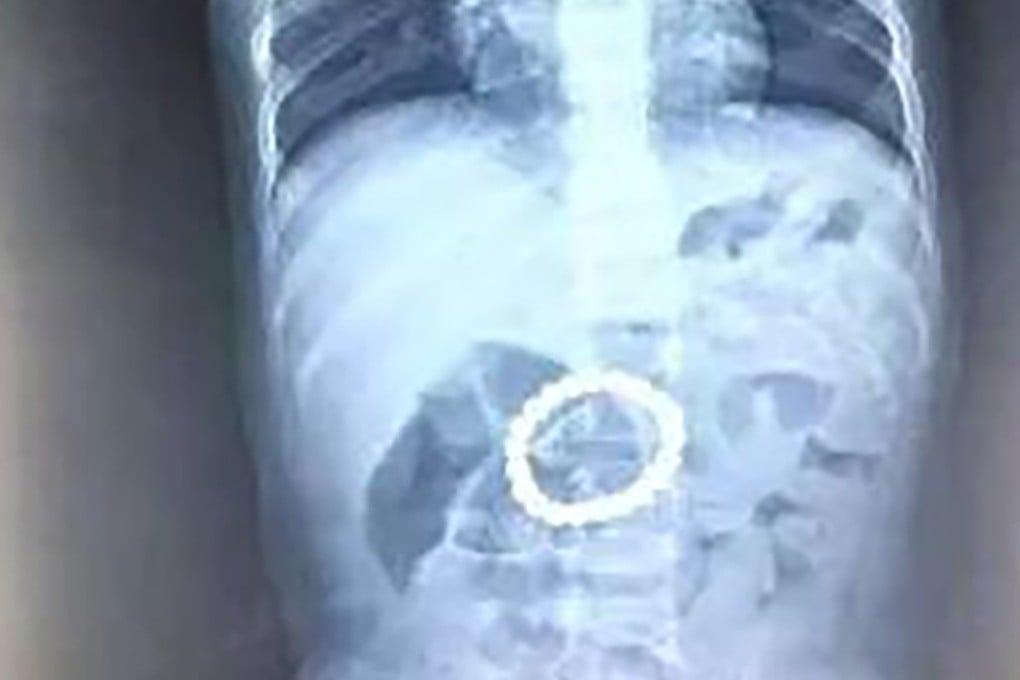

“The beads formed a ring in his stomach, and although we got them all out during the operation, the baby suffered a lot of pain,” she said.